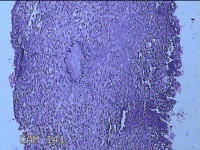

宫腔内容物

性别

女

年龄

39岁

临床诊断

异常子宫出血 重度贫血

一般病史

阴道流血20天,头晕乏力7天。

标本名称

大体所见

灰白暗红色不规则碎组织5.3x4.5x1.3cm一堆。

图2